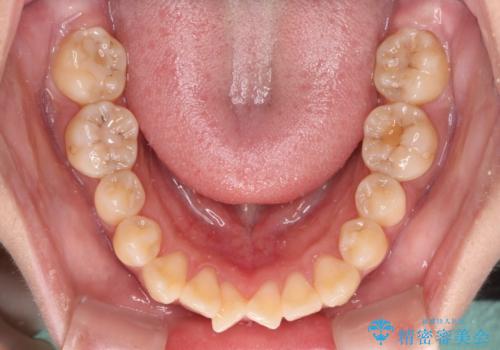

- 上下前歯の非接触と叢生を気にして来院された患者様です。

開咬の改善はインビザラインの最も得意とするところであるため、インビザラインを用いて矯正治療を行うこととしました。

途中海外転勤の可能性が高いとのこともあり、ワイヤー装置ではなくインビザライン矯正が最適な治療ツールとなりました。